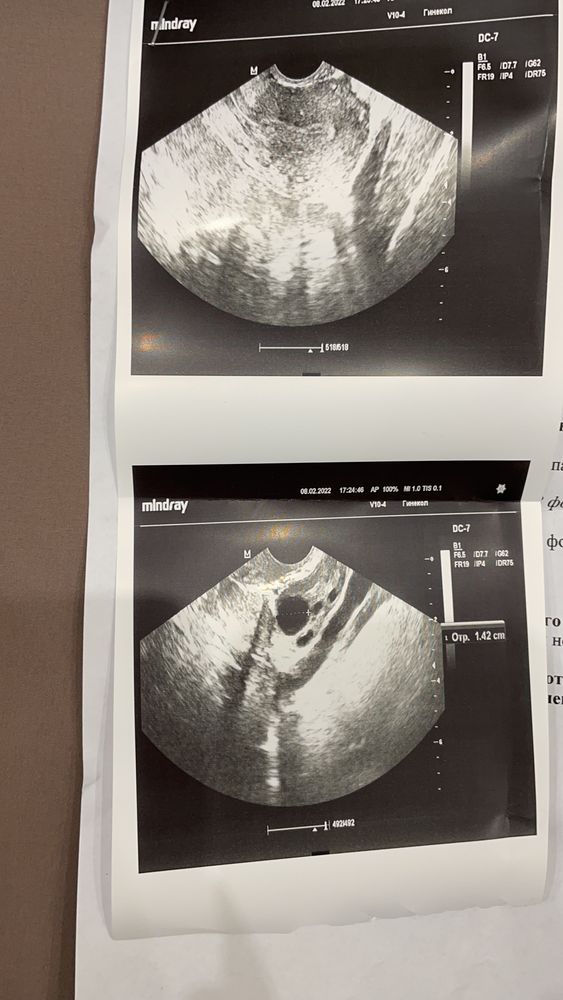

Девушки, сегодня 24дц, тесты на овуляцию молчали, решила сходить на узи и вот что там увидели. Стоит ли надеяться на овуляцию в этом месяце? Цикл нерегулярный, в промежутке 30-37 обычно. Последние 3 месяца было 36,37,30. Было как то 42, 45. Неужели в этом цикле будет за 40 дней😭

Думаю стоит, и проверить тестами на О через 5 дней. Тк домин фолликул лопнет при 24 мм (а растет по 2-3 мм в день) . Тот что 14 скорее всего дорастет раз у вас длинный цикл. А вот на счет эндометрия действительно маловат к овуляции хороший 11-15 мм. Тут больше вопрос кк эндометрию а не к самой овуляции. Найдите хорошего гинеколога.

Эндометрий вообще незрелый на начало цикла,если и лопнет- то тот который до 14,но рост будет медленный,неделя точно,этот цикл и к 50 может приблизиться,если вам правильно намеряли

Возможно что тот макс фолик который сейчас 14 дорастет, у вас скорей всего поздние овуляции, думаю дней через 5-6 нужно повторить, посмотреть

Овуляция возможно и будет, но эндометрий слишком маленький, будет ли прикрепление , остаётся под вопросом, для 2 фазы маловат конечно.

У меня между ДФ 14мм и О дня 3-4, то есть видимо где-то на 28дц будет О

bravo gun, вот только прочитала,в правом яичнике фолликулы до 14мм, это же значит что есть доминантный фолликул 14мм?!

bravo gun, значит он почти 14, доминантный для овуляции это 18 мм,сходите через неделю на УЗИ,раньше точно с вашим эндометрием нет смысла